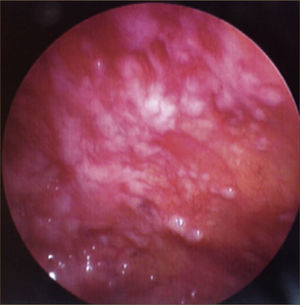

La toracoscopía médica puede ser realizada en sala de endoscopía o en pabellón, con anestesia local y sedación e.v. No requiere intubación. Se accede a la cavidad pleural por un portal de entrada de 10mm, no requiere de estadía en sala de postoperados en forma obligada. Se drena en forma segura todo el derrame contenido en la cavidad pleural y luego se inspecciona la cavidad. Permite tomar biopsias grandes bajo visión directa sobre la pleura parietal, pulmón y diafragma que permitirán hacer estudios moleculares y de inmunohistoquímica al tejido y además permite efectuar pleurodesis en el mismo procedimiento44. (Figuras 5–7).